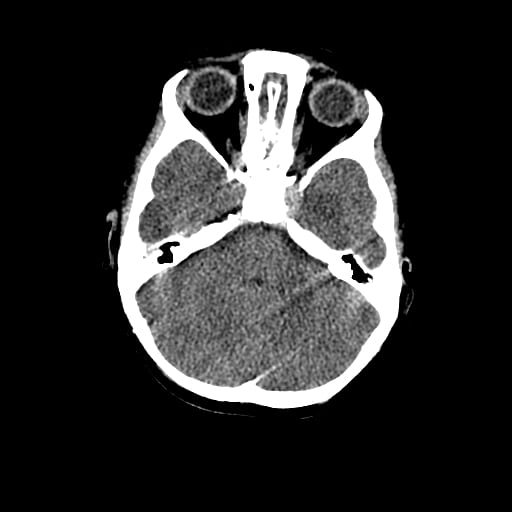

Age: 1

Sex: Male

Indication: Fall